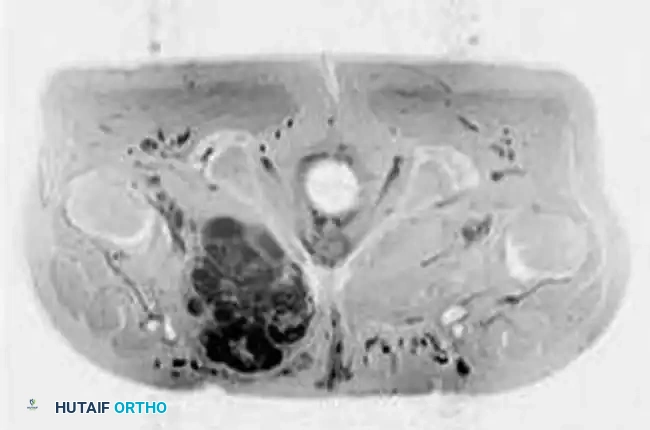

Intraoperative Imaging and Margin Assessment

Continuous intraoperative assessment using fluoroscopy and frozen section pathology is mandatory. The following images demonstrate various stages of complex upper extremity resections, allograft preparations, and prosthetic implantations across the humerus and elbow joint.